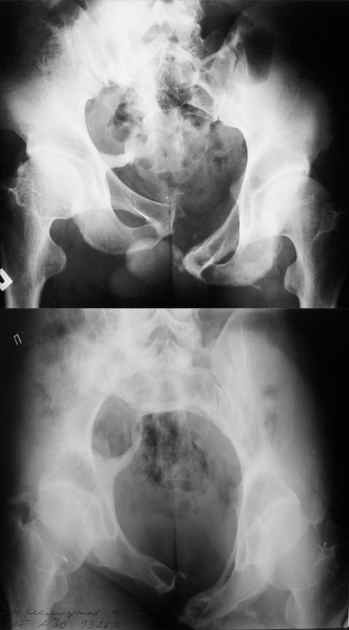

Дорогой Андрей. Мы имеем дело с комбинированной (ротационно и вертикально) нестабильностью таза со смещением правого гнемипелвиса. При таких переломах, фиксация только переднего полукольца вне зависимости от метода фиксации, как уже было сказано Djoldas Kuldjanov, M.D., не может создать адекватной фиксации. И перелом пластины был вполне ожидаемым после активизации пациента. Смещение сохраняется, и по-видимому не 2 см., а все 4, если не более. Разница всего (+2 см) по конечностям как вы указываете, скорее скомпенсировано позвоночником и протезом. Дополнительные снимки или КТ исследование помогли бы уточнить степень смещения с точностью до мм., выявить перелом поперечного отростка пятого поясничного позвонка, или помимо разрыва правого крестцово-подвздошного сочленения выявить перелом боковой массы крестца справа и т.д. При возможности, конечно, все это желательно сделать. Но мало что изменится с практической точки зрения, т.к. задача - это низведение репозиция и надежная фиксация правого гемипелвиса. Учитывая плачевный опыт стержневого аппарата, давность травмы совершенно очевидно, что поставленная задача достижима при открытой репозиции и одномоментной фиксации переднего полукольца с артродезированием правого крестцово-подвздошного сустава. Операция выполняется в положении больного на здоровом боку или полубоку из расширенного трансоссального подвздошно-пахового доступа с переходом на лонное сочленение доступом по Pfannenstiel. Указанный доступ обеспечивает подход к крестцово-подвздошному сочленению как спереди так и сзади. После артродезирования выполняется синтез лонного сочленения. Клинический пример

Пациентка С.26 лет. Травма за 6 месяцев до поступления

Укорочение правой нижней конечности до 10см

23.09.2003. Одновременный остеосинтез переднего и заднего тазовых полуколец

Результат через 10 дней

и 8месяцев после операции